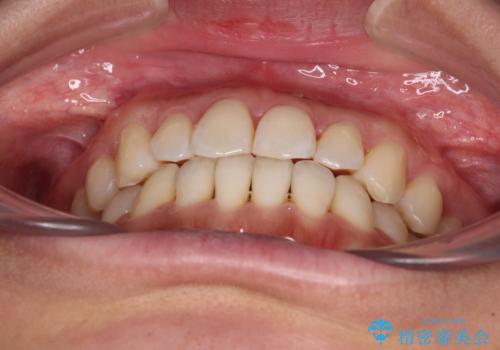

- 前歯のデコボコで前方に出ていることを気にして来院された患者様です。

上顎前歯が捻れて前方に飛び出しており、下顎前歯もそれに沿うようにデコボコとなっていました。

IPR(歯と歯の間を削る処置)によりスペースを獲得して上下顎前歯のデコボコを改善し、飛び出している前歯が引っ込むように設定し、インビザラインにて矯正治療を行うこととしました。